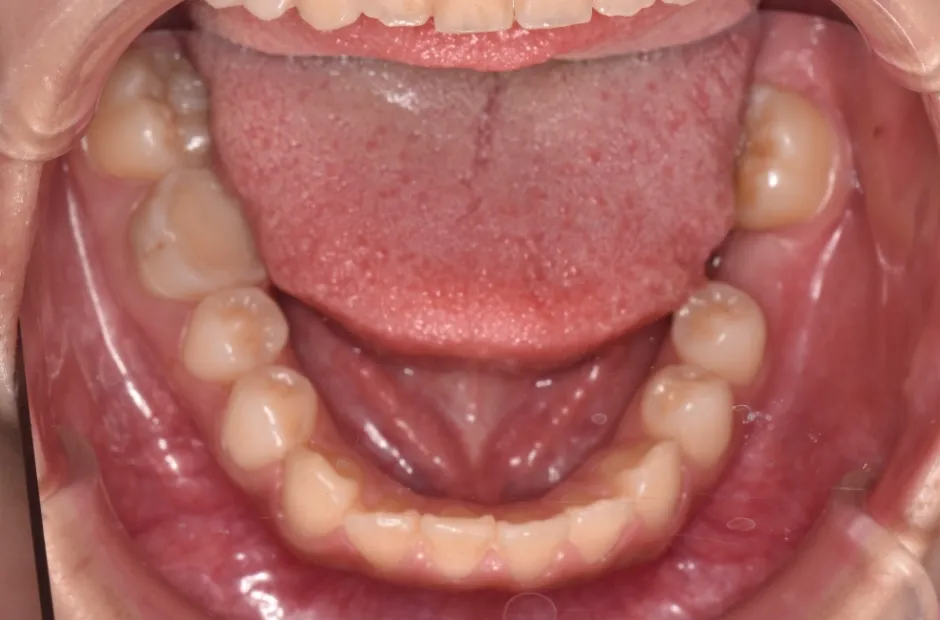

叢生

| 診断名・主訴 | 叢生 |

|---|---|

| 年齢・性別 | 43歳・女性 |

| 治療期間・回数 | 2年7か月 27回 |

| 治療に用いた主な装置 | 舌側矯正 |

| 抜歯部位 | 両顎4,4 |

| 治療費 | 100万円(税抜) |

| リスク・副作用 | 装置による違和感・疼痛・歯肉退縮・歯根吸収・虫歯のリスクなど |

治療前